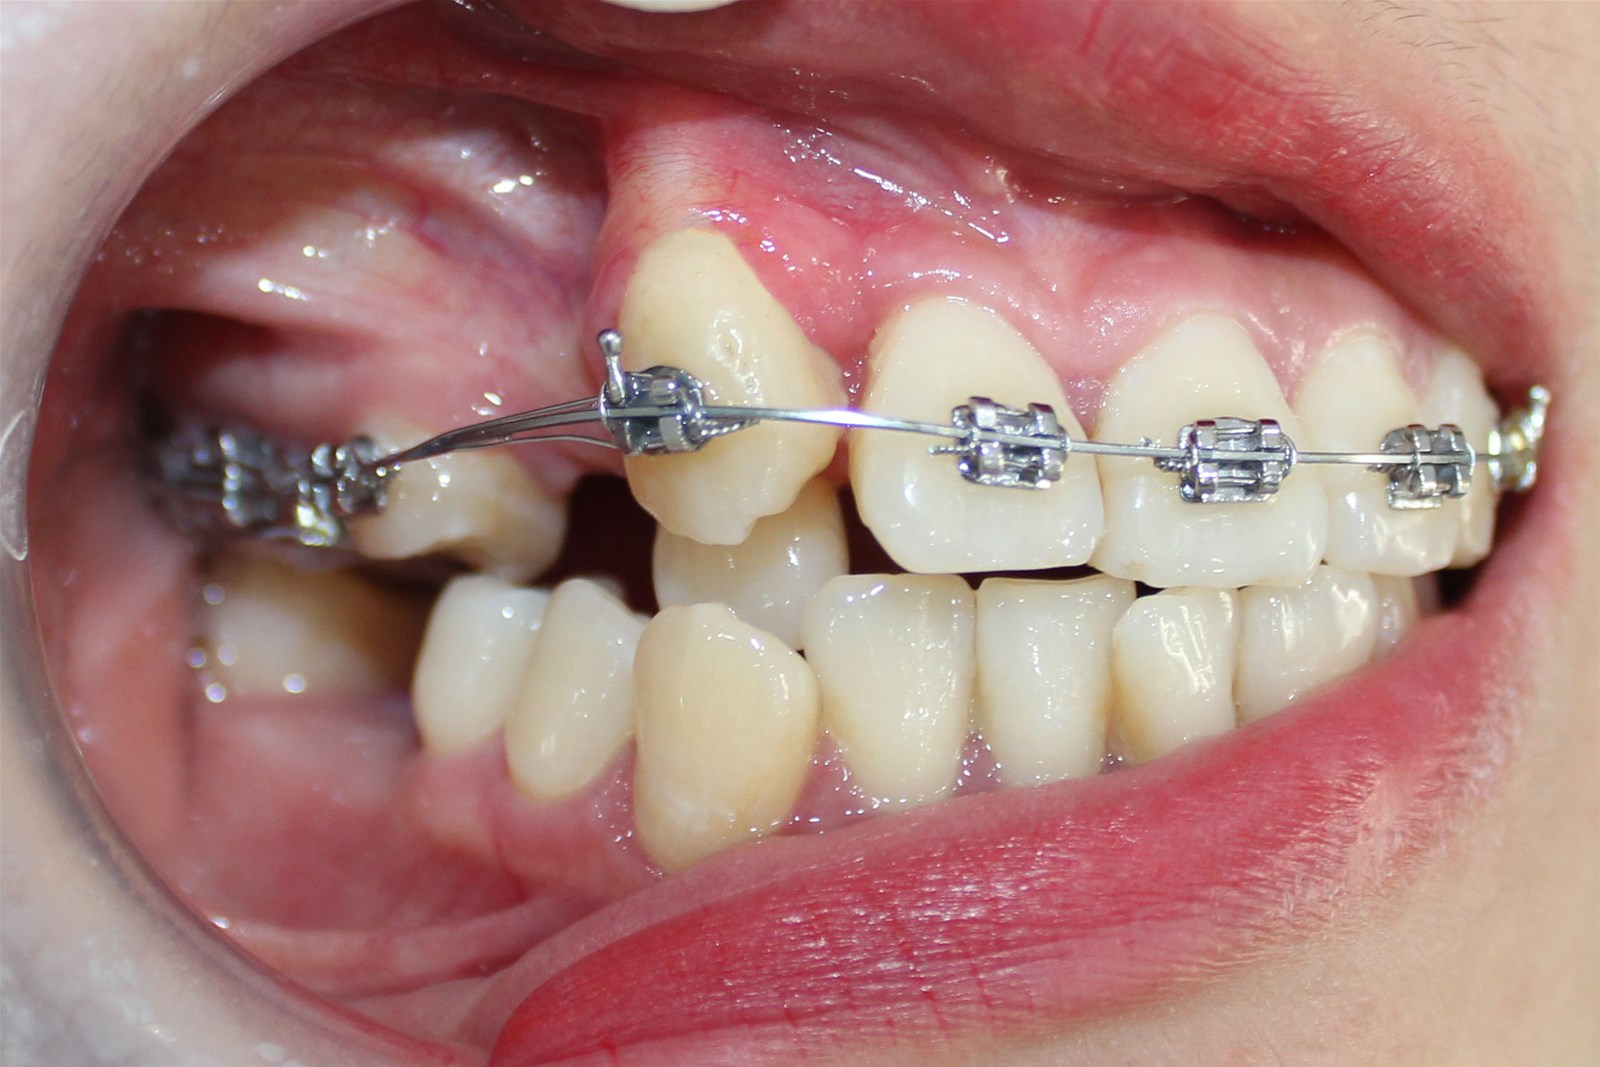

Khi mất răng hàm số 6 hàm trên hoặc hàm dưới có niềng được không? Câu trả lời là có thể niềng răng để khắc phục việc mất răng hàm số 6. Tuy nhiên điều này phụ thuộc vào nhiều yếu tố. Nếu bạn đã mọc hoặc đang mọc răng khôn (răng hàm số 8), hoặc nếu răng khôn mọc ngầm nhưng vẫn có thể tiếp cận, niềng răng là một phương án khả thi. Tuy nhiên, nếu không có răng khôn hoặc đã nhổ răng khôn mà vẫn mất răng hàm số 6, niềng răng không phải là giải pháp. Trong trường hợp này, cần phải thực hiện thủ thuật cấy ghép implant cho răng đã mất.

Nếu vẫn còn răng số 7 và răng số 8 cùng hàm và cùng phía, có thể niềng răng bằng cách kéo 2 răng này thay vị trí của răng số 6. Theo thời gian kéo và điều chỉnh, răng số 7 sẽ thay vị trí của răng hàm số 6 và trở thành răng số 6, còn răng số 8 sẽ thay vị trí của răng số 7 và trở thành răng số 7. Sau khi hoàn thành quá trình niềng răng, bạn sẽ có một hàm thật và có thể ăn uống tự nhiên như trước khi mất răng.

Cũng có thể thực hiện tương tự đối với trường hợp răng số 8 đang mọc, tuy nhiên, việc này phụ thuộc vào tình trạng răng số 8 và tình trạng răng hiện tại của bạn, và sẽ được nha sĩ chỉ định.

Quá trình niềng răng sẽ yêu cầu tính toán kỹ lưỡng để đảm bảo răng số 7 dịch chuyển vào vị trí của răng hàm số 6 một cách hiệu quả, đồng thời cũng cần xác định thời gian điều chỉnh răng phù hợp. Trong trường hợp khoảng trống mất răng nhỏ, quá trình niềng răng sẽ dễ dàng hơn, tuy nhiên, nếu khoảng trống lớn, việc này có thể không đạt được hiệu quả mong muốn. Trong trường hợp này, bạn có thể cần phải tiến hành trồng thêm răng số 6 đã mất để phục hồi cấu trúc răng sau khi hoàn tất quá trình niềng răng.